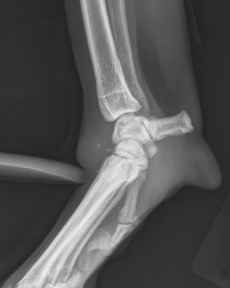

A carpal hyperextension injury occurs when the wrist joint (carpus) bends backward beyond its normal range of motion,

overstretching or tearing the ligaments that stabilize it. This usually happens when a pet falls or jumps from a height, landing with the paw flat

or even bent backward against the ground. The key supporting structures — the palmar fibrocartilage and

palmar ligaments — are essential for preventing the carpus from collapsing under weight.

Once torn, these ligaments cannot heal reliably to their original strength or length. As a result, the carpus remains unstable,

and the wrist continues to collapse during weight-bearing.

Standard radiographs (X-rays) may not show ligament tears, so stress radiographs — which gently flex or extend the joint to reveal abnormal motion —

are necessary to confirm and localize the injury.